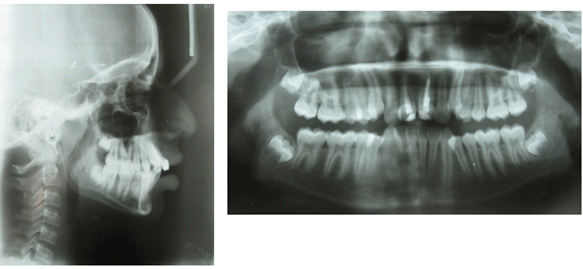

A 14-year-old boy presented to our department with a chief complaint of irregular arrangement of upper and lower teeth. On extraoral examination patient had mesoprosopic, grossly symmetrical face, convex profile with incompetent lips (Figure 1) and (Figure 2). He had a history of trauma to upper anterior teeth at the age of 12 years. On intraoral examination he had Angle's Class-I molar relationship bilaterally with severe crowding in both upper and lower teeth. Both the maxillary central incisors had composite restorations and were severely discolored (Figure 1) (Figure 2). The periapical radiograph showed fractured crowns of both the maxillary central incisors with endodontic treatment of both and a faint fracture line in the apical third of right maxillary incisor (Figure 3). The fracture line was confirmed by taking another periapical radiograph at different tube angle. Although clinically, maxillary central incisors were asymptomatic, but their long-term prognosis was questionable.

Figure 2: Pretreatment lateral cephalogram and orthopantomogram.